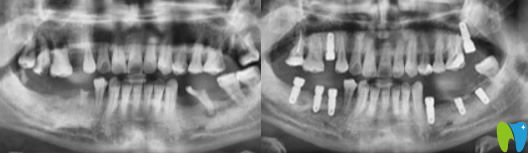

術(shù)前問題:下頜磨牙掉的只剩一顆,上頜情況也不容樂觀,并有多顆牙松動(dòng)。

解決方案:通過數(shù)字化技術(shù),精準(zhǔn)地在梁女士缺牙位置植入種植體,一些無法保留的牙齒采取了即拔即種治療,解決了她多年的缺牙問題。